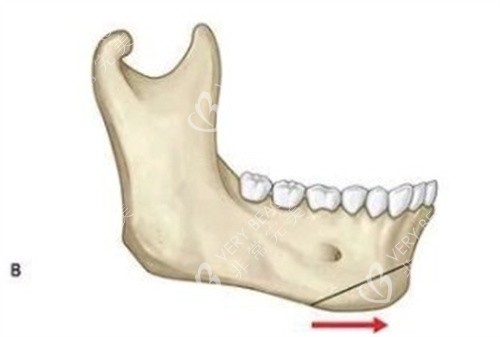

牵张成骨术,是一种内源性骨组织工程技术,通过外科手段将骨骼切开,在切骨线两侧安装特制的牵张器,经过一定的延迟期后,缓慢牵张切骨间隙,使间隙不断增宽,并激发机体组织再生的潜力,在牵张间隙内不断形成新生骨组织。同时,该技术还能使骨骼周围的肌肉、神经、血管、皮肤等软组织同期延长,从而达到延长骨骼、改善形态的目的。

颅面畸形矫正:如小下颌畸形(mandibular micrognathia)、半侧颜面发育不全综合症(hemifacial microsomia)以及各种颅面畸形综合症,如Nager syndrome、Pierre-Robin syndrome、Crouzon syndrome、Treacher-Collins syndrome、Craniofacial synostosis等。